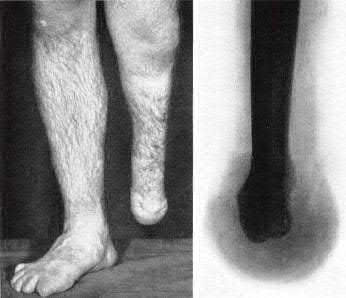

Question 3:

A 15-year-old boy presents with a permeative lytic lesion in the femoral diaphysis with aggressive periosteal reaction ('onion skinning'). Biopsy reveals uniform small round blue cells. Cytogenetic analysis of this tumor will most likely demonstrate which of the following translocations?

Correct Answer: t(11;22)

Explanation:

The clinical and radiographic description is classic for Ewing sarcoma. The characteristic cytogenetic abnormality is a balanced translocation t(11;22)(q24;q12), which fuses the EWS gene on chromosome 22 with the FLI1 gene on chromosome 11. This is seen in approximately 85-90% of Ewing sarcomas. t(9;22) is the Philadelphia chromosome (CML), t(X;18) is seen in synovial sarcoma, t(2;13) in alveolar rhabdomyosarcoma, and t(12;16) in myxoid liposarcoma.